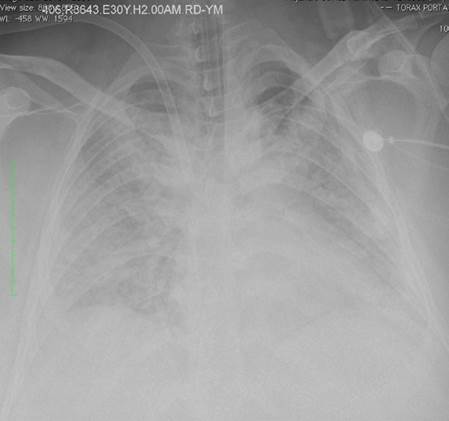

Todos los pacientes tuvieron SDRA grave de conformidad con la definición de Berlín3, y se canularon para ECMO VV si tenían una relación persistente de presión parcial de oxígeno/fracción inspirada de oxígeno (PaFI) < 100, con una fracción inspirada de oxígeno > 90% a pesar de tratamiento médico óptimo durante 6 horas o menos. Los pacientes remitidos de otras instituciones se transportaron por vía aérea o terrestre. En la Figura 1 aparece una radiografía de tórax en un paciente con SDRA.

FUENTE: Autores.

FIGURA 1 Radiografía de tórax en un paciente con síndrome de dificultad respiratoria del adulto (SDRA).